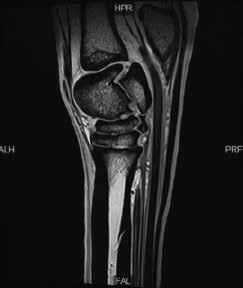

addition, the use of rehabilitation, such as with therapeutic exercise programs, can stimulate many horses to repair tendon injuries with better fiber alignment and decrease rates of reinjury in the long term compared with prolonged stall rest. Rehabilitation specialists will be able to work with you to recommend exercises to maintain your horses core strength and mobility while not in exercise, as something that will make returning them to full strength easier once they are back in work. Some injuries are actually better treated with rest. These are bone bruises that do best when your horse rests. This is why magnetic resonance imaging or MRI is sometimes recommended when radiographs and ultrasound are not giving answers as to what is going on. An MRI allows you to look at the bone detail in high resolution to diagnose injury to the bone or soft tissue structures (like tendons or ligaments) that radiographs and ultrasound are unable to accomplish. Above is an example of what an MRI of a hock looks like. Regular recheck veterinary examinations during the rehabilitation process allows for early identification of minor setbacks that can be addressed with changes in the rehabilitation exercises, addition of medication or therapies, and ultimately provide you with peace of mind that you are doing the right thing for your horse at every stage of their healing.